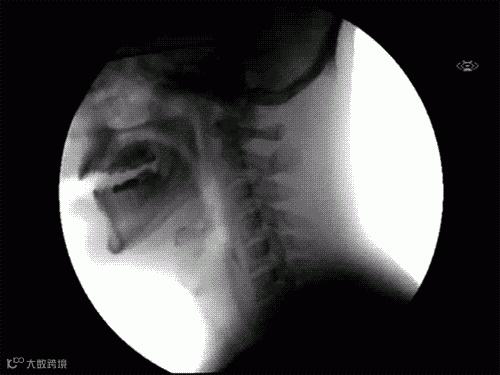

7.人是怎么吞东西的?